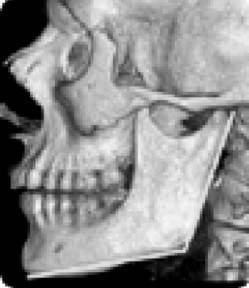

Еще одно сообщение Phys-Org: руководитель службы пластической и реконструктивной хирургии в американской университетской клинике Говард Лэнгстайн (Howard Langstein) на основании своих многочисленных исследований утверждает, что с возрастом происходит изменение угла нижней челюсти (показанные желтым цветом), длина и высота самого тела челюсти (рис. 10).

Рис. 10. Череп молодого человека

Рис. 10а. Череп старого человека

А поскольку нижняя челюсть является основной костью лицевой части лица, любые ее изменения влияют на общий вид лица.

Внешне это проявляется в том, что его нижняя часть приобретает более вялые очертания, мягкие ткани провисают, овал теряет свою четкость, снижается тонус кожи щек, подбородка и шеи, в результате чего очертания лица приобретают характерный возрастной вид. Далее Г. Лэнгстайн добавил: «Хотя врачи всегда знали, что кости со временем меняются, но как это проявляется с возрастом – не смогли оценить до конца».